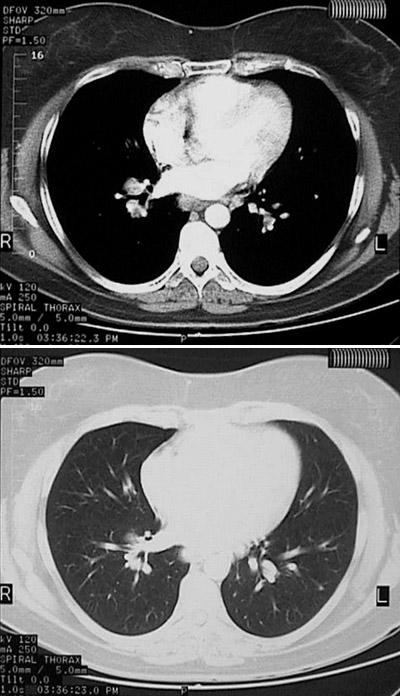

The CT panel at the top with "soft tissue" window and the lower panel with "lung" window setting illustrate scattered bright pulmonary nodules of sarcoidosis along with

prominent hilar adenopathy

.